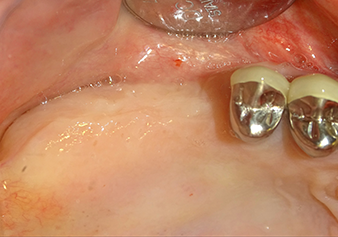

49-летняя пациентка, некурящая и не имеющая ничего примечательного в общей истории болезни, была направлена в нашу хирургическую стоматологическую клинику для хирургического удаления зуба 16 и последующей имплантации. После удаления зуба пациентка перенесла синусит в легкой форме, в результате чего мы сначала выждали шесть месяцев перед проведением операции. Остаточная высота кости при запланированном положении имплантата составляла 3-4 мм (рис. 1 и 2).

Для перемещения аугментационного материала в направлении верхнечелюстной пазухи атравматично, имплантат вводился очень медленно вручную (рис. 9). При этом мембрана еще раз выталкивалась в краниальном направлении. Через два месяца место операции зажило без раздражения. Через шесть месяцев рентгеновский контроль показал значительное увеличение помутнения, что свидетельствует об оссификации (рис. 10). Протезирование было проведено металлокерамической коронкой.